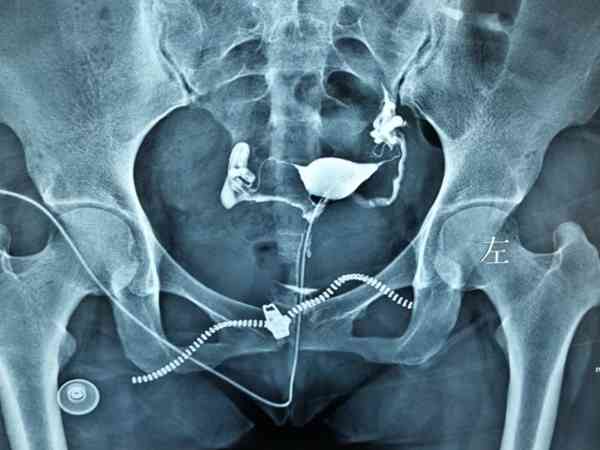

输卵管造影经X线的子宫输卵管造影是通过导管向宫腔及输卵管注入造影剂,利用X线诊断仪行X线透视及摄片,根据造影剂在输卵管及盆腔内的显影情况来了解输卵管是否通畅、阻塞部位及宫腔形态的一种检查方法,很多人听说它是一项手术都认为其过程很麻烦,但其实输卵管造影流程还是很简单的。输卵管造影手术过程是什么输卵管造影是临床上应用较为广泛的方法之一。经X线的子宫输卵管造影是通过导管向宫腔及输卵管注入造影剂,利用X线...

输卵管造影是要用X线观察造影剂的流动情况,从而判断是否存在堵塞或者其他情况,这种检查输卵管是否存在问题的准确率非常高,基本上已经达到了98%左右,所以检查后发现问题最好及时治疗,如果是常规的输卵管堵塞可能会存在不孕的情况,但若是因为盆腔炎所导致的输卵管堵塞的话,患者还会出现腹痛、分泌物增多等情况,可以自行判断。输卵管造影中文名输卵管造影术适应证不孕症、子宫肿瘤等检查时间月经后3-7天就诊科室妇科检...